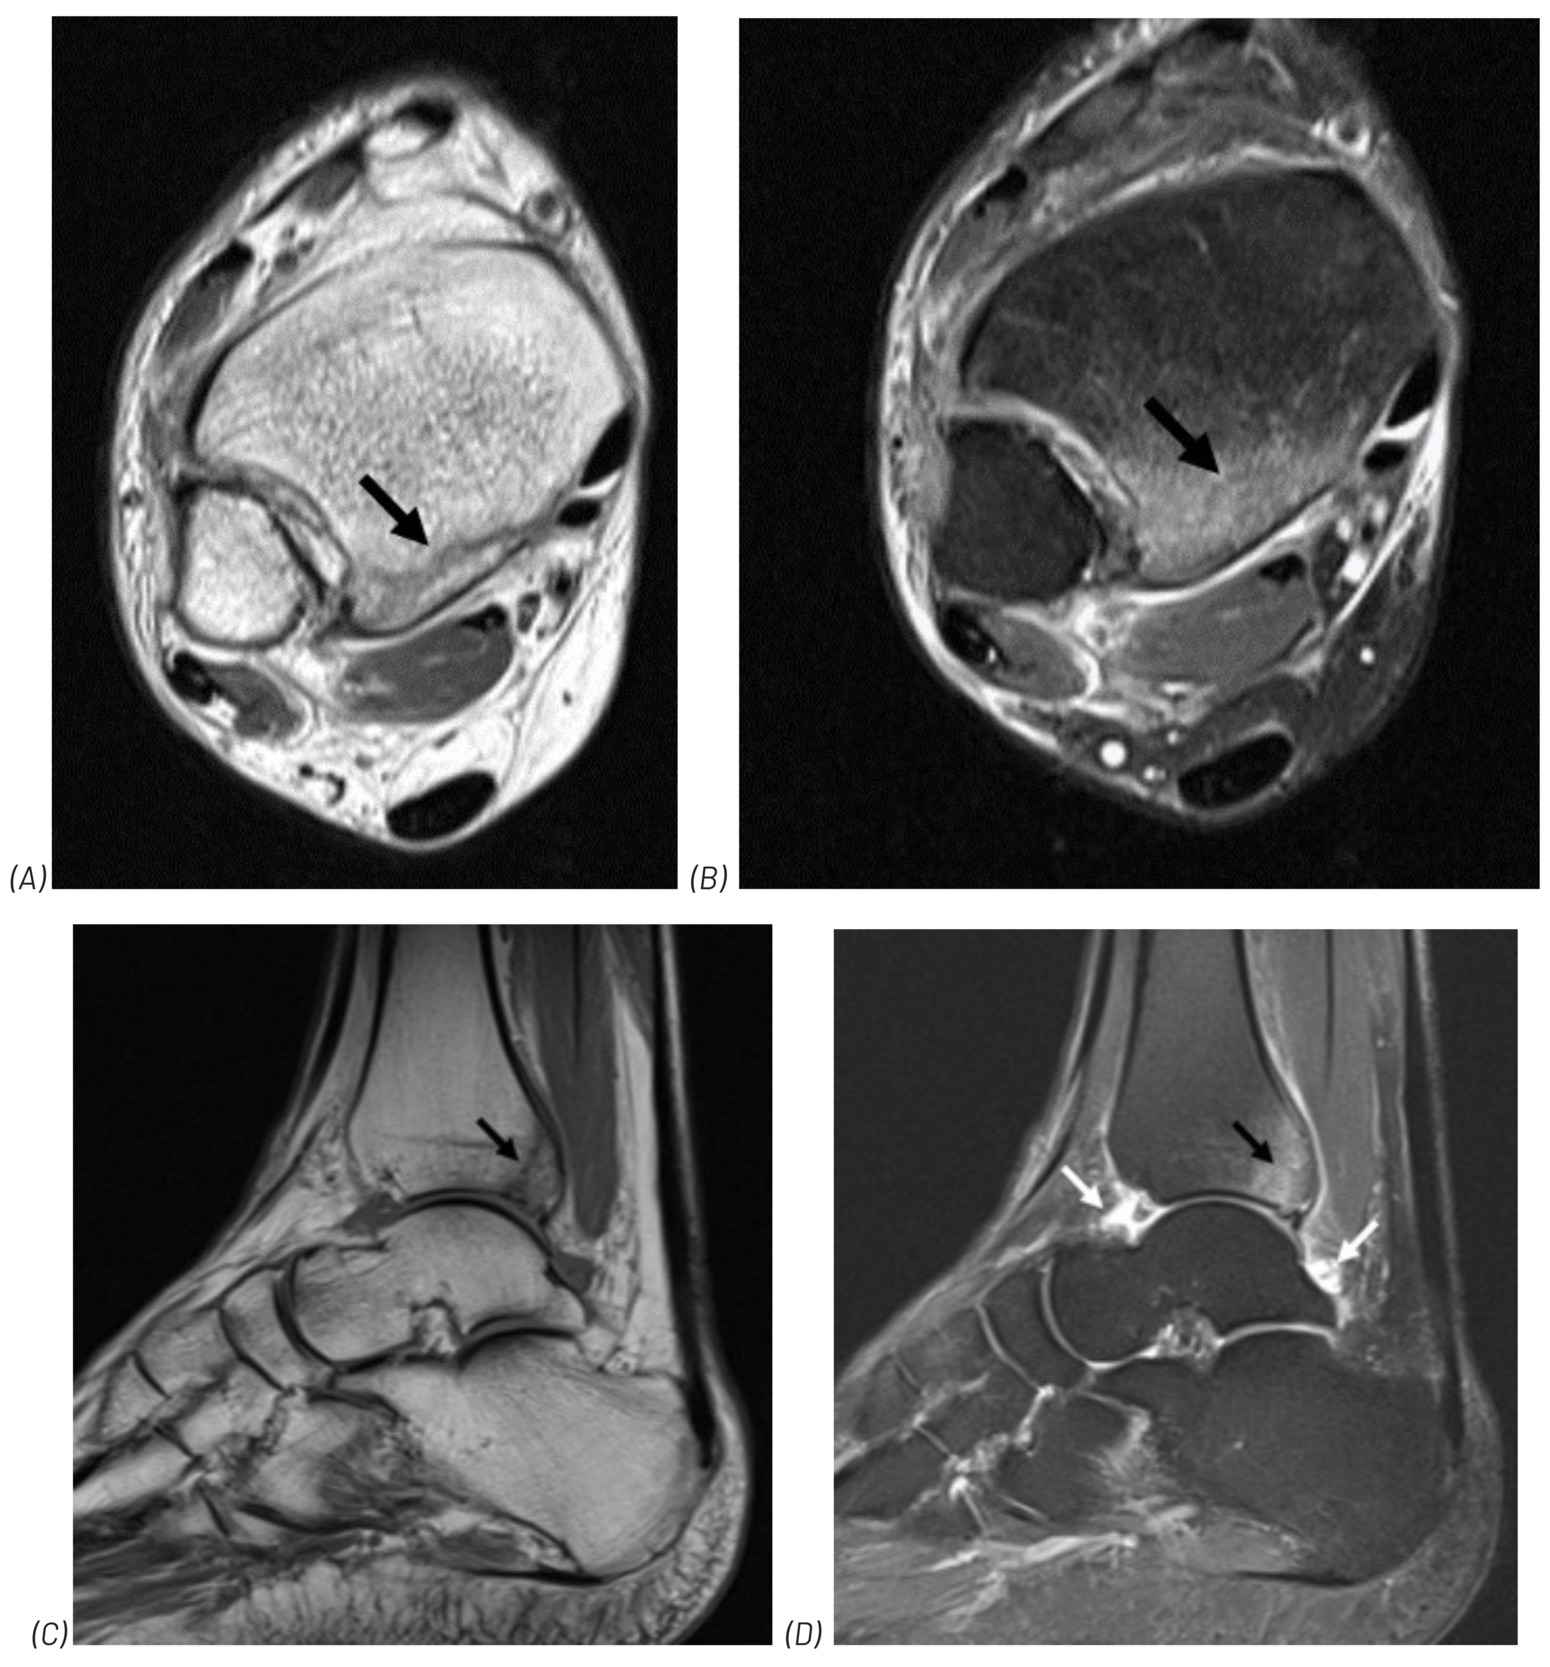

In a second paper, by LaCourt et al (LaCourt S, Sergent A, Richardson M, Carter S. Challenging the Ottawa Ankle Rules: a clinical case study. J Contemporary Chiropr 2024;7:146-149) the author inadvertently included incorrect figures. The correct figures appear in the pdf version that accompanies the html online version. The corrected figures appear below (the original were stretched out).